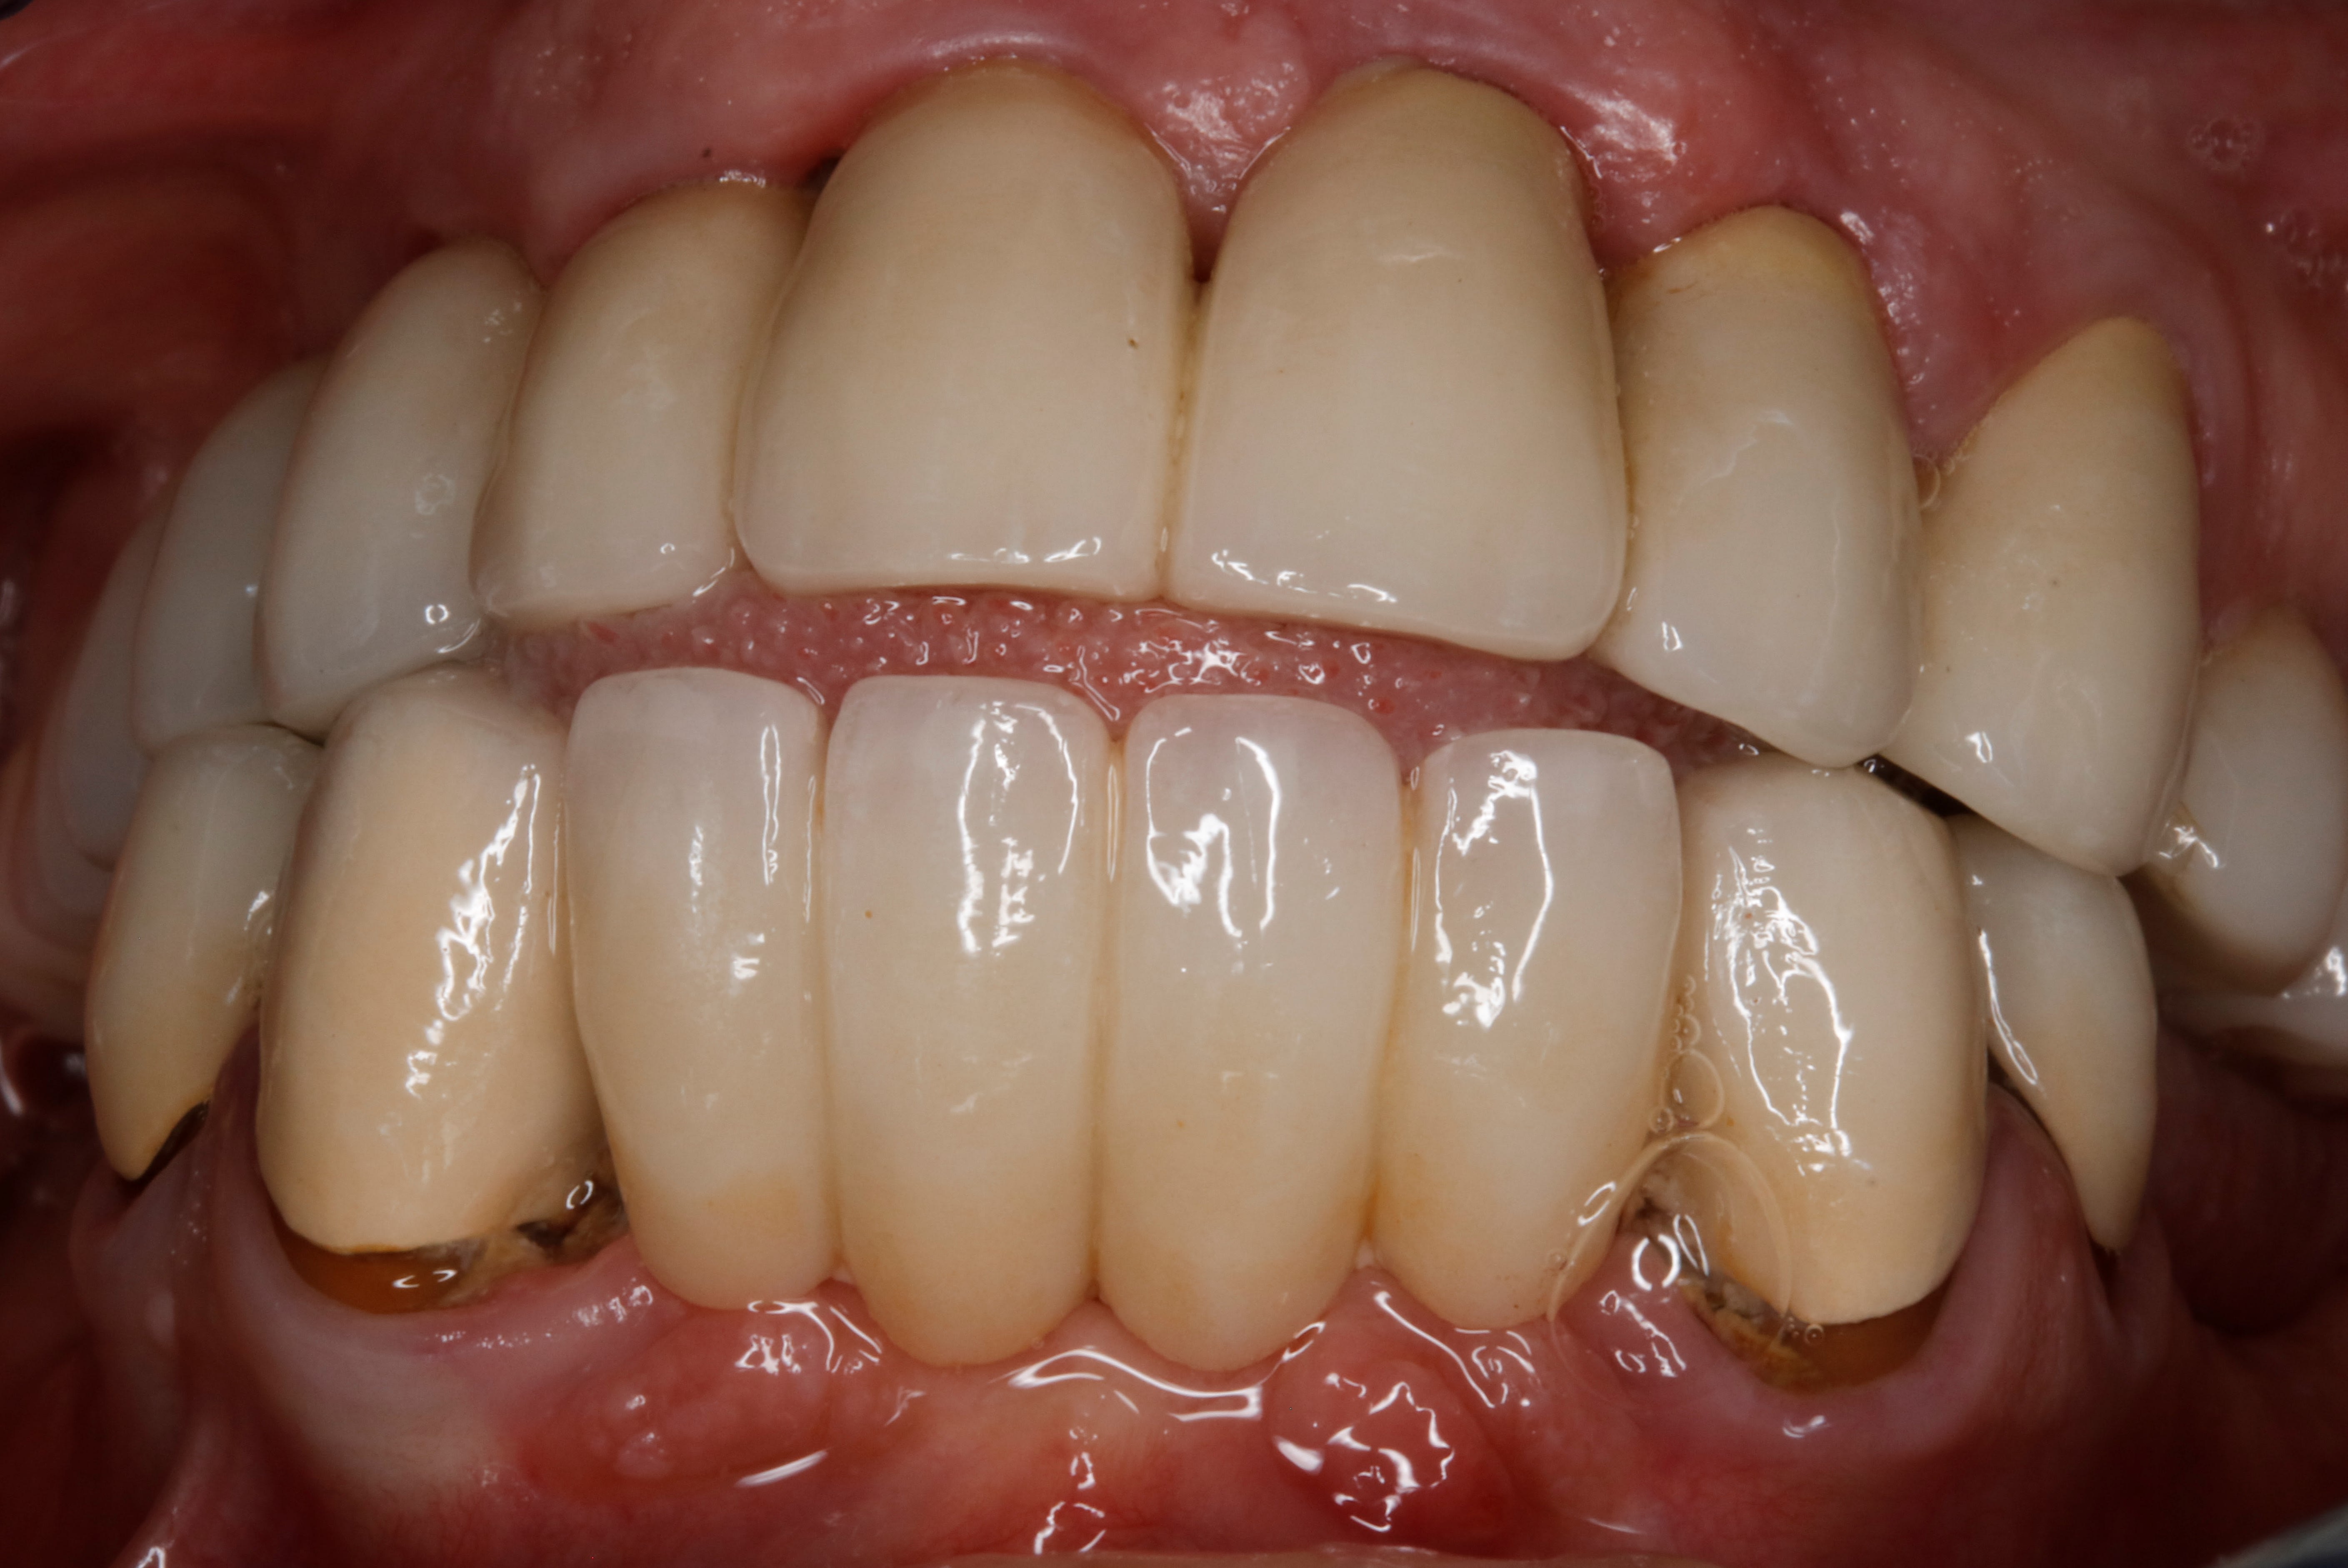

comme vous avez étés tres sage , j ai convoqué le cas de la béance

donc 10 ans après on en est là .

vises un peu les masséters puissants .

on s en sort bien .

de face .

10 ans apres on s en sort bien !

ç est pas mieux de l autre coté finalement , là j ai une autre photo , ç est symétrique

mg 1949 mwqxr7 - Eugenol